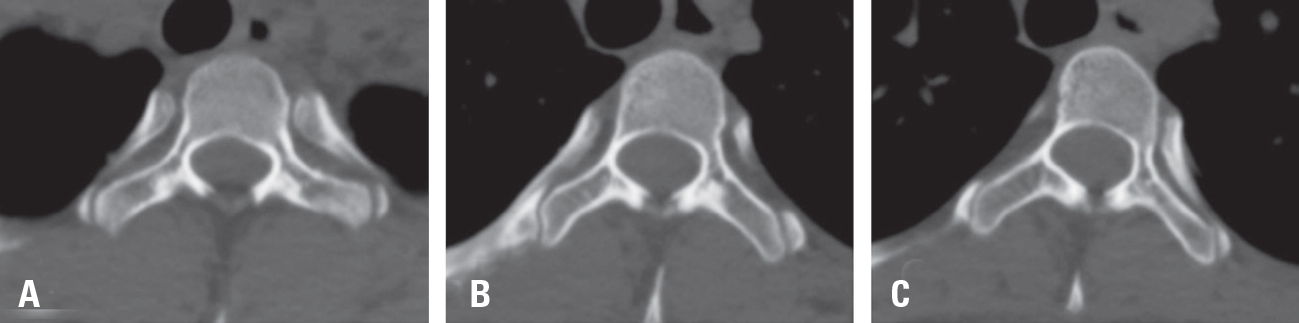

Fig. 4.Axial CT scan image of Adolescent Idiopathic Scoliosis, demonstrating that the pedicle at T2 is relatively wide compared with those at T3 and T4. (A) The pedicle width on the concave side T2 was also measured to be sufficiently wide at 2.8 mm. (B, C) In contrast, the concave-side pedicles at T3 and T4 were measured to be extremely narrow, at 0.6 mm and 0.4 mm, respectively.